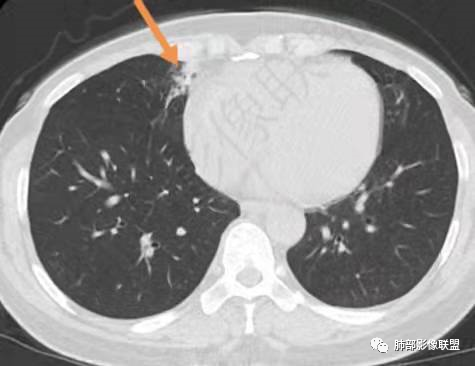

影像特点:右肺上叶混合磨玻璃影,边界清晰,结构松散,内有多结节堆积及支气管扩张影,可见小叶间隔增厚,并局部增厚的小叶间隔上亦存在微结节,胸膜侧可见纤细索条,病灶周围可见多发微结节影。

总体分析:从病灶分布来看符合结核的好发位置,影像表现也符合结核的多态性,且出现卫星灶。由于有边界清晰的GGO,需要鉴别腺癌,虽然此病例有边界清晰的GGO,但是它的GGO的边缘有结节感,呈多结节堆积,而腺癌的GGO缺乏这种“多结节堆积感”,另外,此病例也没有发现腺癌的胸膜凹陷征、毛刺征及月牙铲等。

间质性肺结核是结核的一种特殊影像学表现,为继发性肺结核,影像学表现与常见的继发性肺结核有所不同,有一定的特征性。

1、年轻人多见,一般提示免疫力可能有下降。 2、好发部位与其它结核类似,上叶及下叶背段为主。 3、烟花征,反晕征,环呈结节状,可以伴随空洞,树芽征,结节灶,胸水。(反晕征:一般周围实性环形高密度影,中央丛密度低;一般环超过圆的3/4,结核的环主要是小叶核心结节组成,类似于多发树芽征聚集,边缘结节感。中央的晕:可以是腺泡结节,树芽征,细网状,磨玻璃影,很少正常,主要成分是小叶内间质增厚、小叶核心结节、肺泡内病变。)其实也体现了结核的多灶性、多态性特点。

一般来说,间质性结核主要是实性来源的;开始是气道播散为主,主要表现最多的是树芽征,然后是腺泡结节,相互之间可融合形成片状,往往这些病人有个前提,免疫力相对低下,然后侵袭到附近的间质里面去。首先树芽征,表现在呼吸性细支气管炎及终末细支气管炎的一些粘液栓,前提是支气管壁增厚引起的;当免疫力下降时结核杆菌会沿着小叶核心区域沿着壁朝外蔓延,进入间质,而小叶核心最明显。因为在核心的细支气管周围,所以表现出类似于树芽征样,也是分枝状的。当然,前提是本身里面小叶细支气管里面的粘液栓,所以支气管显示不出,病变表现类似于树芽征一样的结节影,这些病变如果周围一圈连在一起,类似反晕征的环堤,中央区域,肺泡壁被侵犯,会呈现磨玻璃影及细网状影等。